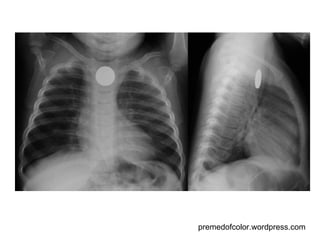

premedofcolor.wordpress.com

Sistema Respiratório Nariz, boca, faringe, laringe, traquéia  e árvore brônquica  Dois pulmões

Sistema Respiratório Nariz,boca, faringe, laringe, traquéia e árvore brônquica Dois pulmões